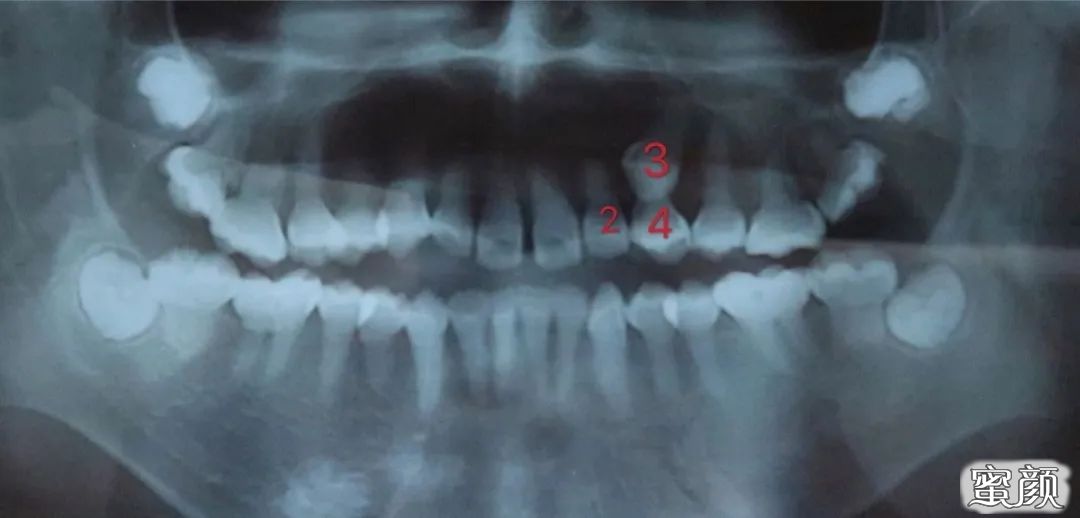

通过X片我们可以清楚看见左上虎牙低位埋伏阻生尖牙,牙冠与侧切牙牙根较接近。

检查:口内检查左上乳牙C滞留(外观与恒牙3相似)处拍摄X-Ray显示左上乳牙C阻生伴多生牙一颗。

术前x片